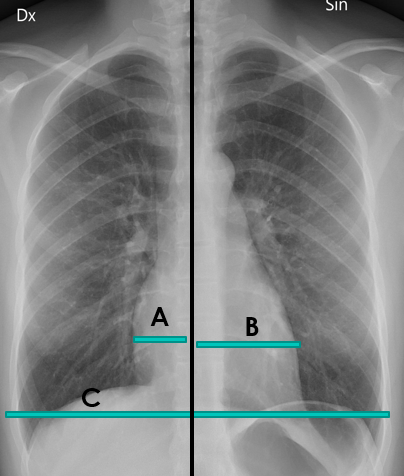

Silueta Cardíaca: Calcular índice cardiotorácico:

- Se traza una línea media.

- Se mide la distancia entre el punto más distal de cada borde cardíaco (aurícula derecha y ventrículo izquierdo) y se suman.

- Se mide el diámetro transversal de la caja torácica.

- Se divide el primer dígito por el segundo.

En adultos el valor normal es < 0,50 cm. Un valor superior a este, es indicativo de cardiomegalia.

Imagen hecha por el autor